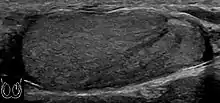

Fibrotic striations

A striated pattern of the testicle, radiating from its mediastinum, does not have clinical importance unless there are alarming symptoms or abnormal signal on Doppler ultrasonography.[6] It is presumed to represent fibrosis.[6]